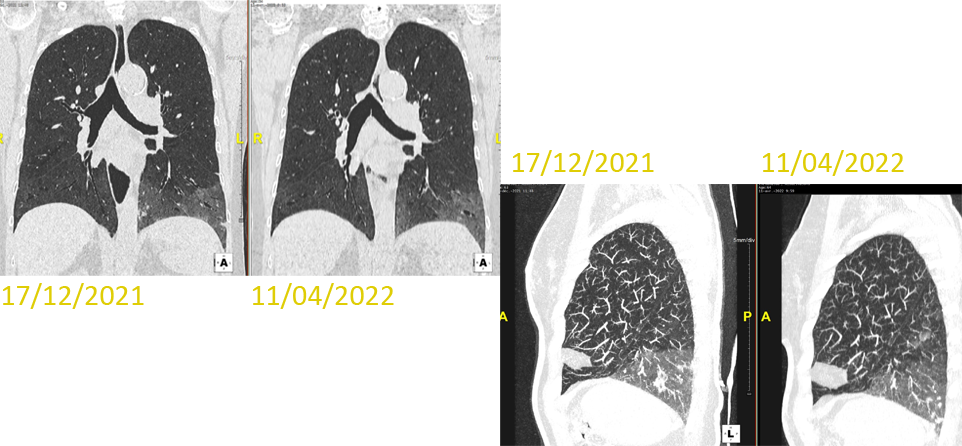

Patiente 67 ans, dyspnée stade II, toux au décubitus, Hernie hiatale & RGO; Raynaud récent. Amaigrissement -3kgs.

Maladie systémique connue depuis 2009.

Télangiectasies cutanées & sclérodactylie; ATCD d’ulcérations pulpaires. Pas d’atteinte pulmonaire ou rénale.

Endoscopie & LBA négatifs. ECHO CARDIO et KT droit <0.

QUEL EST VOTRE DIAGNOSTIC ?